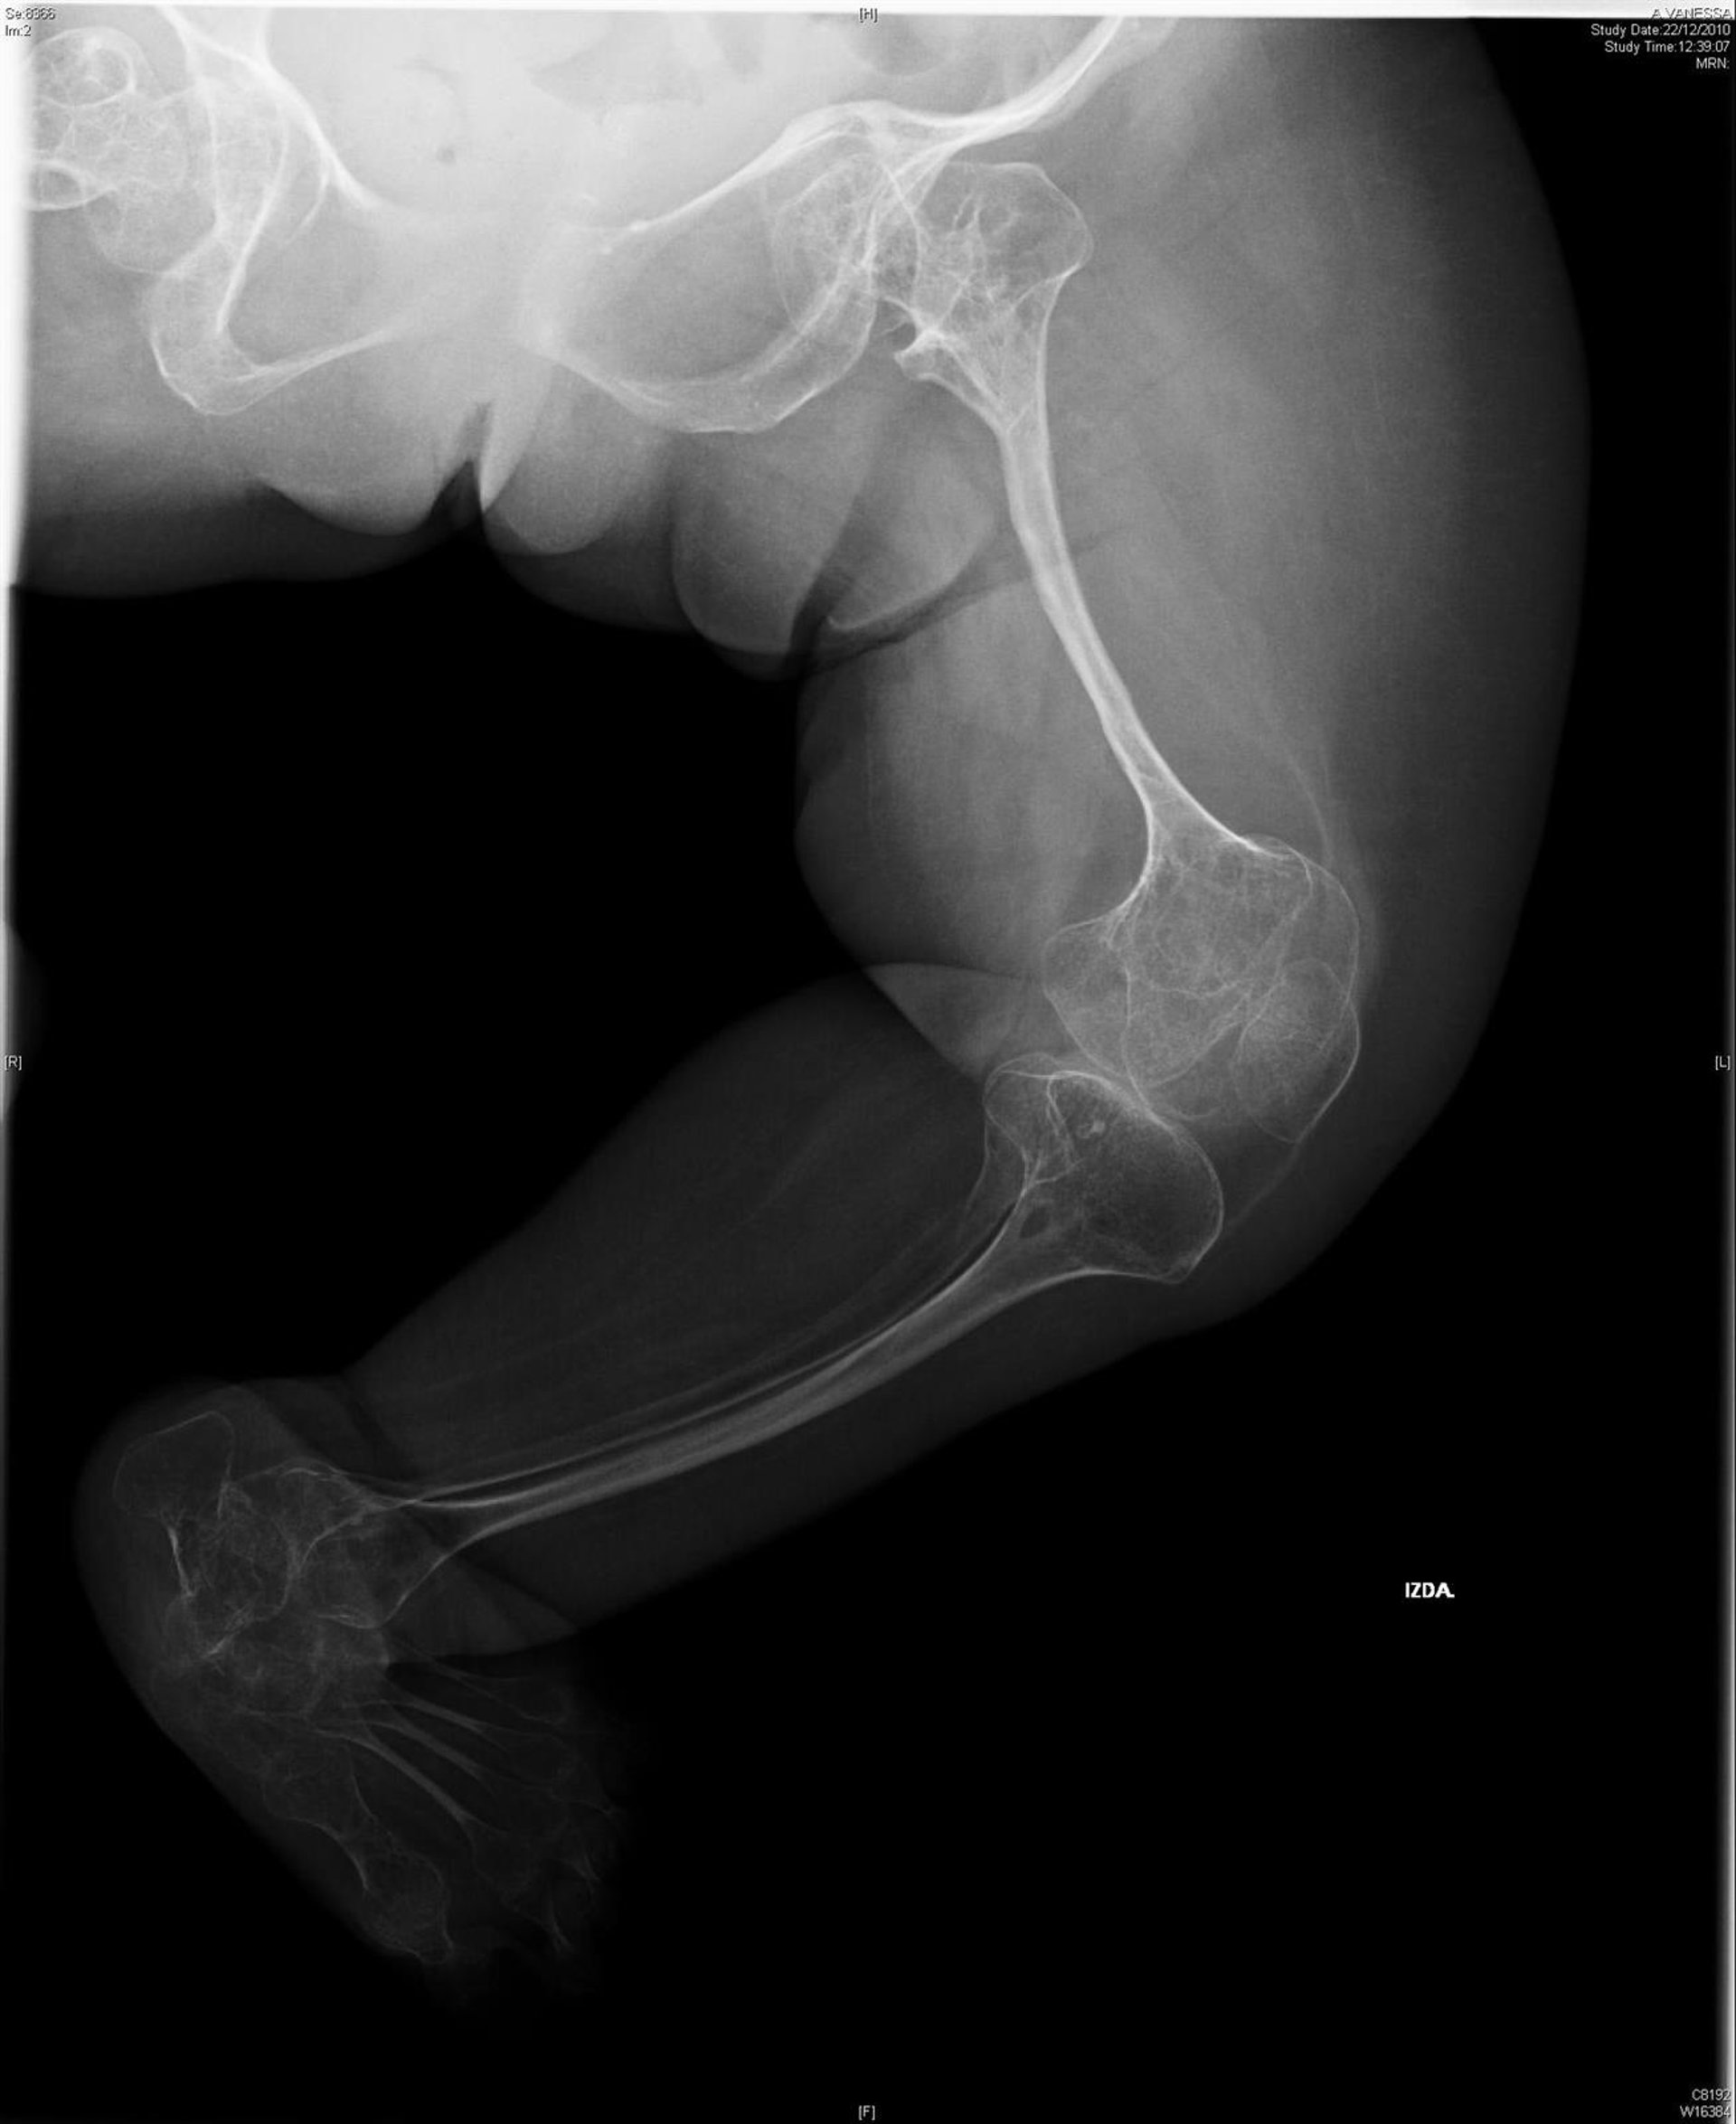

Una nueva técnica desarrollada por científicos de la Universidad de Glasgow (Reino Unido) podría ayudar a liberar un tratamiento para la regeneración ósea, desarrollar mejores terapias para lesiones de médula, injertos óseos y otras cirugías.

En este sentido, los factores de crecimiento juegan un papel fundamental en la biología del desarrollo, tanto en el crecimiento como en el envejecimiento. Trabajos previos han demostrado como una proteína morfogenética ósea 2 o 'BMP-2', podría ayudar a fomentar la regeneración del hueso en pacientes.

"El hueso es el segundo más comúnmente injertado en la medicina después de la sangre, lo que significa que hay muchas aplicaciones potenciales para este proceso. Por ejemplo, las personas que han sufrido lesiones en accidentes de tráfico, o perdido áreas significativas del hueso durante los tratamientos de cáncer podrían ser tratados con mayor eficacia a través de estas técnicas", ha concluido.